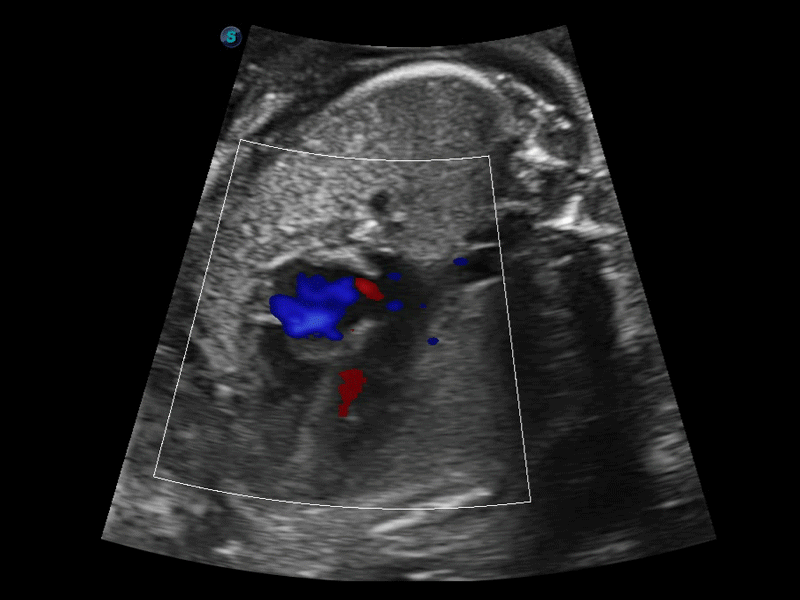

SR Flow高分辨率血流成像

高分辨率血流成像技术提高了对低速血流信号的检测能力。在提高空间分辨率的同时,也克服了血流外溢现象,为用户提供更加真实的血流动力学信息。